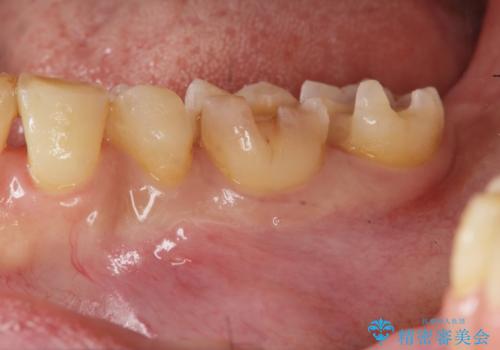

銀歯の下で虫歯の再発 拡大鏡下で行う虫歯の精密治療

- 他院で銀歯の下部に再発した虫歯の存在を指摘され、精密な治療を求めて来院されました。

銀歯下に虫歯が再発すると神経に近くなり、根管治療を必要とする可能性が高まってしまいます。

健全な歯を削らないように拡大鏡下で丁寧に虫歯を除去することで神経を温存し精密なセラミック治療を行うことができました。